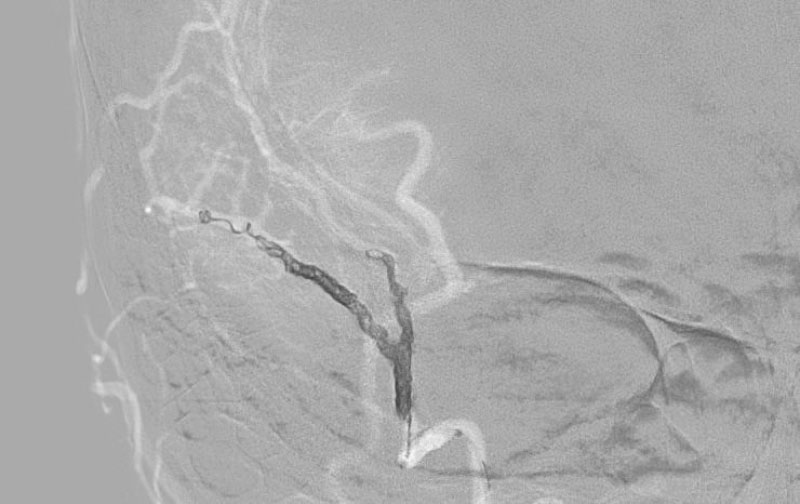

症例 '25年11月

No.

1598

'25年11月26日

右円蓋部髄膜腫

40代

大阪府の病院

手術写真

治療

前

中

後